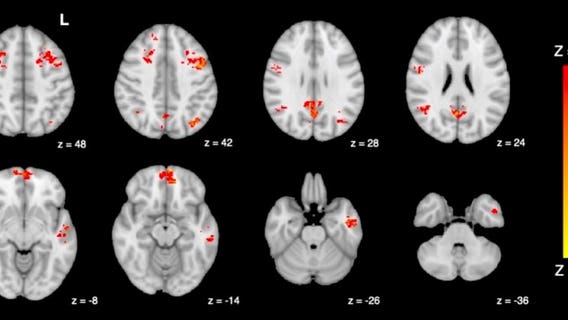

Sitting in traffic for just 2 hours can lead to brain damage, study shows

The study is the first of its kind to present evidence supporting a connection between air pollution and cognition.